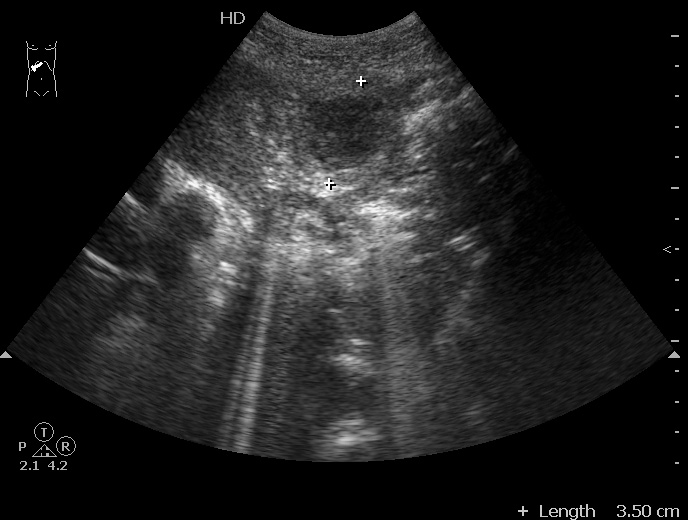

#3

08-09-04-134127_KRAYNOVA_20.jpg

Типичная картина ##1-4:

Гипоэхогенное неоднородное округлое образование, окруженное эхогенным "демаркационным валом"

измененной паренхимы печени.